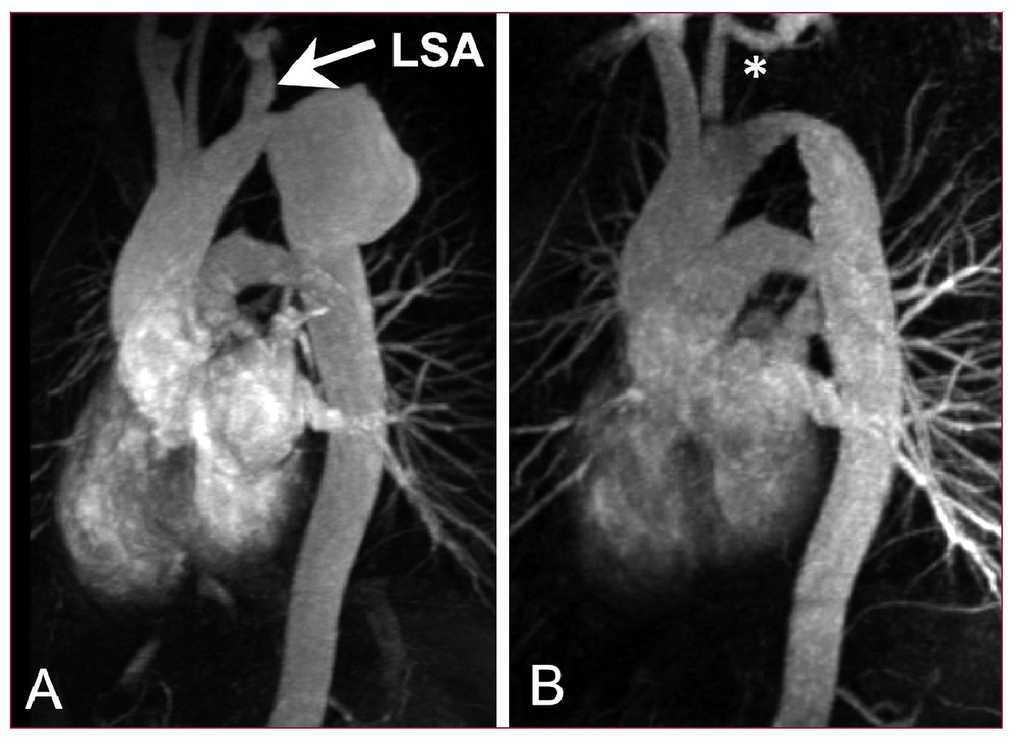

Rotura Traumática de la Aorta

Es resultado de un mecanismo de deceleración/aceleración produciendo fuerzas de cizallamiento en la pared aórtica en la unión entre estos dos segmentos de la

aorta.

Manifestación Clínica:

-Pulsos distintos en extremidades superiores.

-Diferencia en las presiones arteriales Superiores e inferiores.

-Signos de Shock.

Tratamiento.

-Transporte rápido.

-O2 en altas concentraciones.

-Acceso IV y Líquidos IV prudentemente.